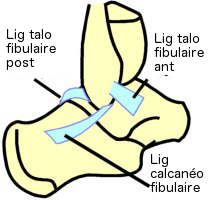

Le ligament collatéral latéral

possède 3 faisceaux qui irradient de la malléole latérale :

- Faisceau antérieur (lig. talo fibulaire ant.) est tendu

du bord antérieur de la malléole latérale à la face

externe du col du talus

- Faisceau moyen (lig. calcanéo-fibulaire) est tendu du

bord antérieur de la malléole latérale à la face externe

du calcanéus

- Faisceau postérieur (lig. talo-fibulaire post.) est

tendu de la face interne de la malléole latérale à la face

postérieure du talus

|

Vue

latérale pied D

|